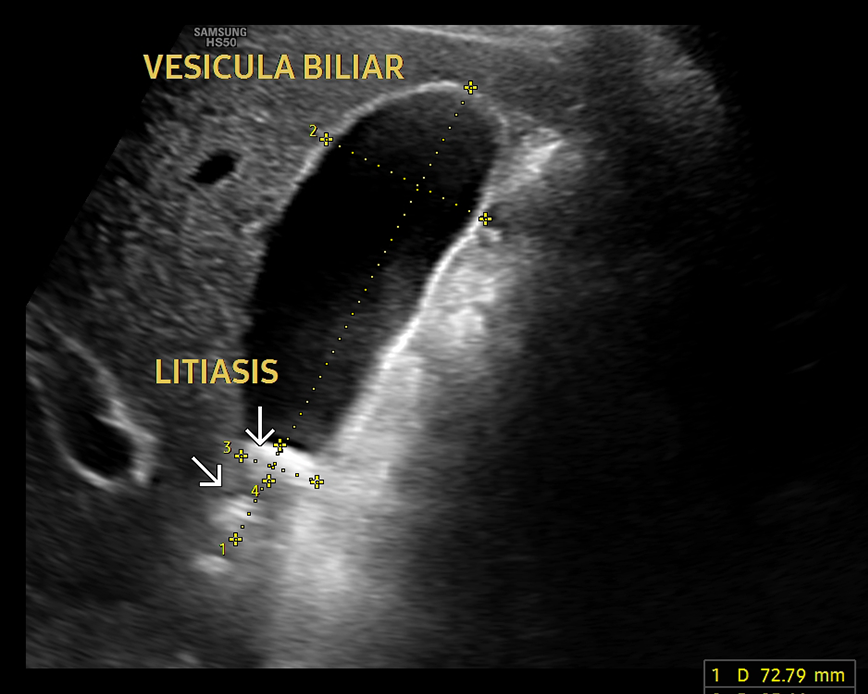

- Estudio de la vesicular biliar y vías biliares